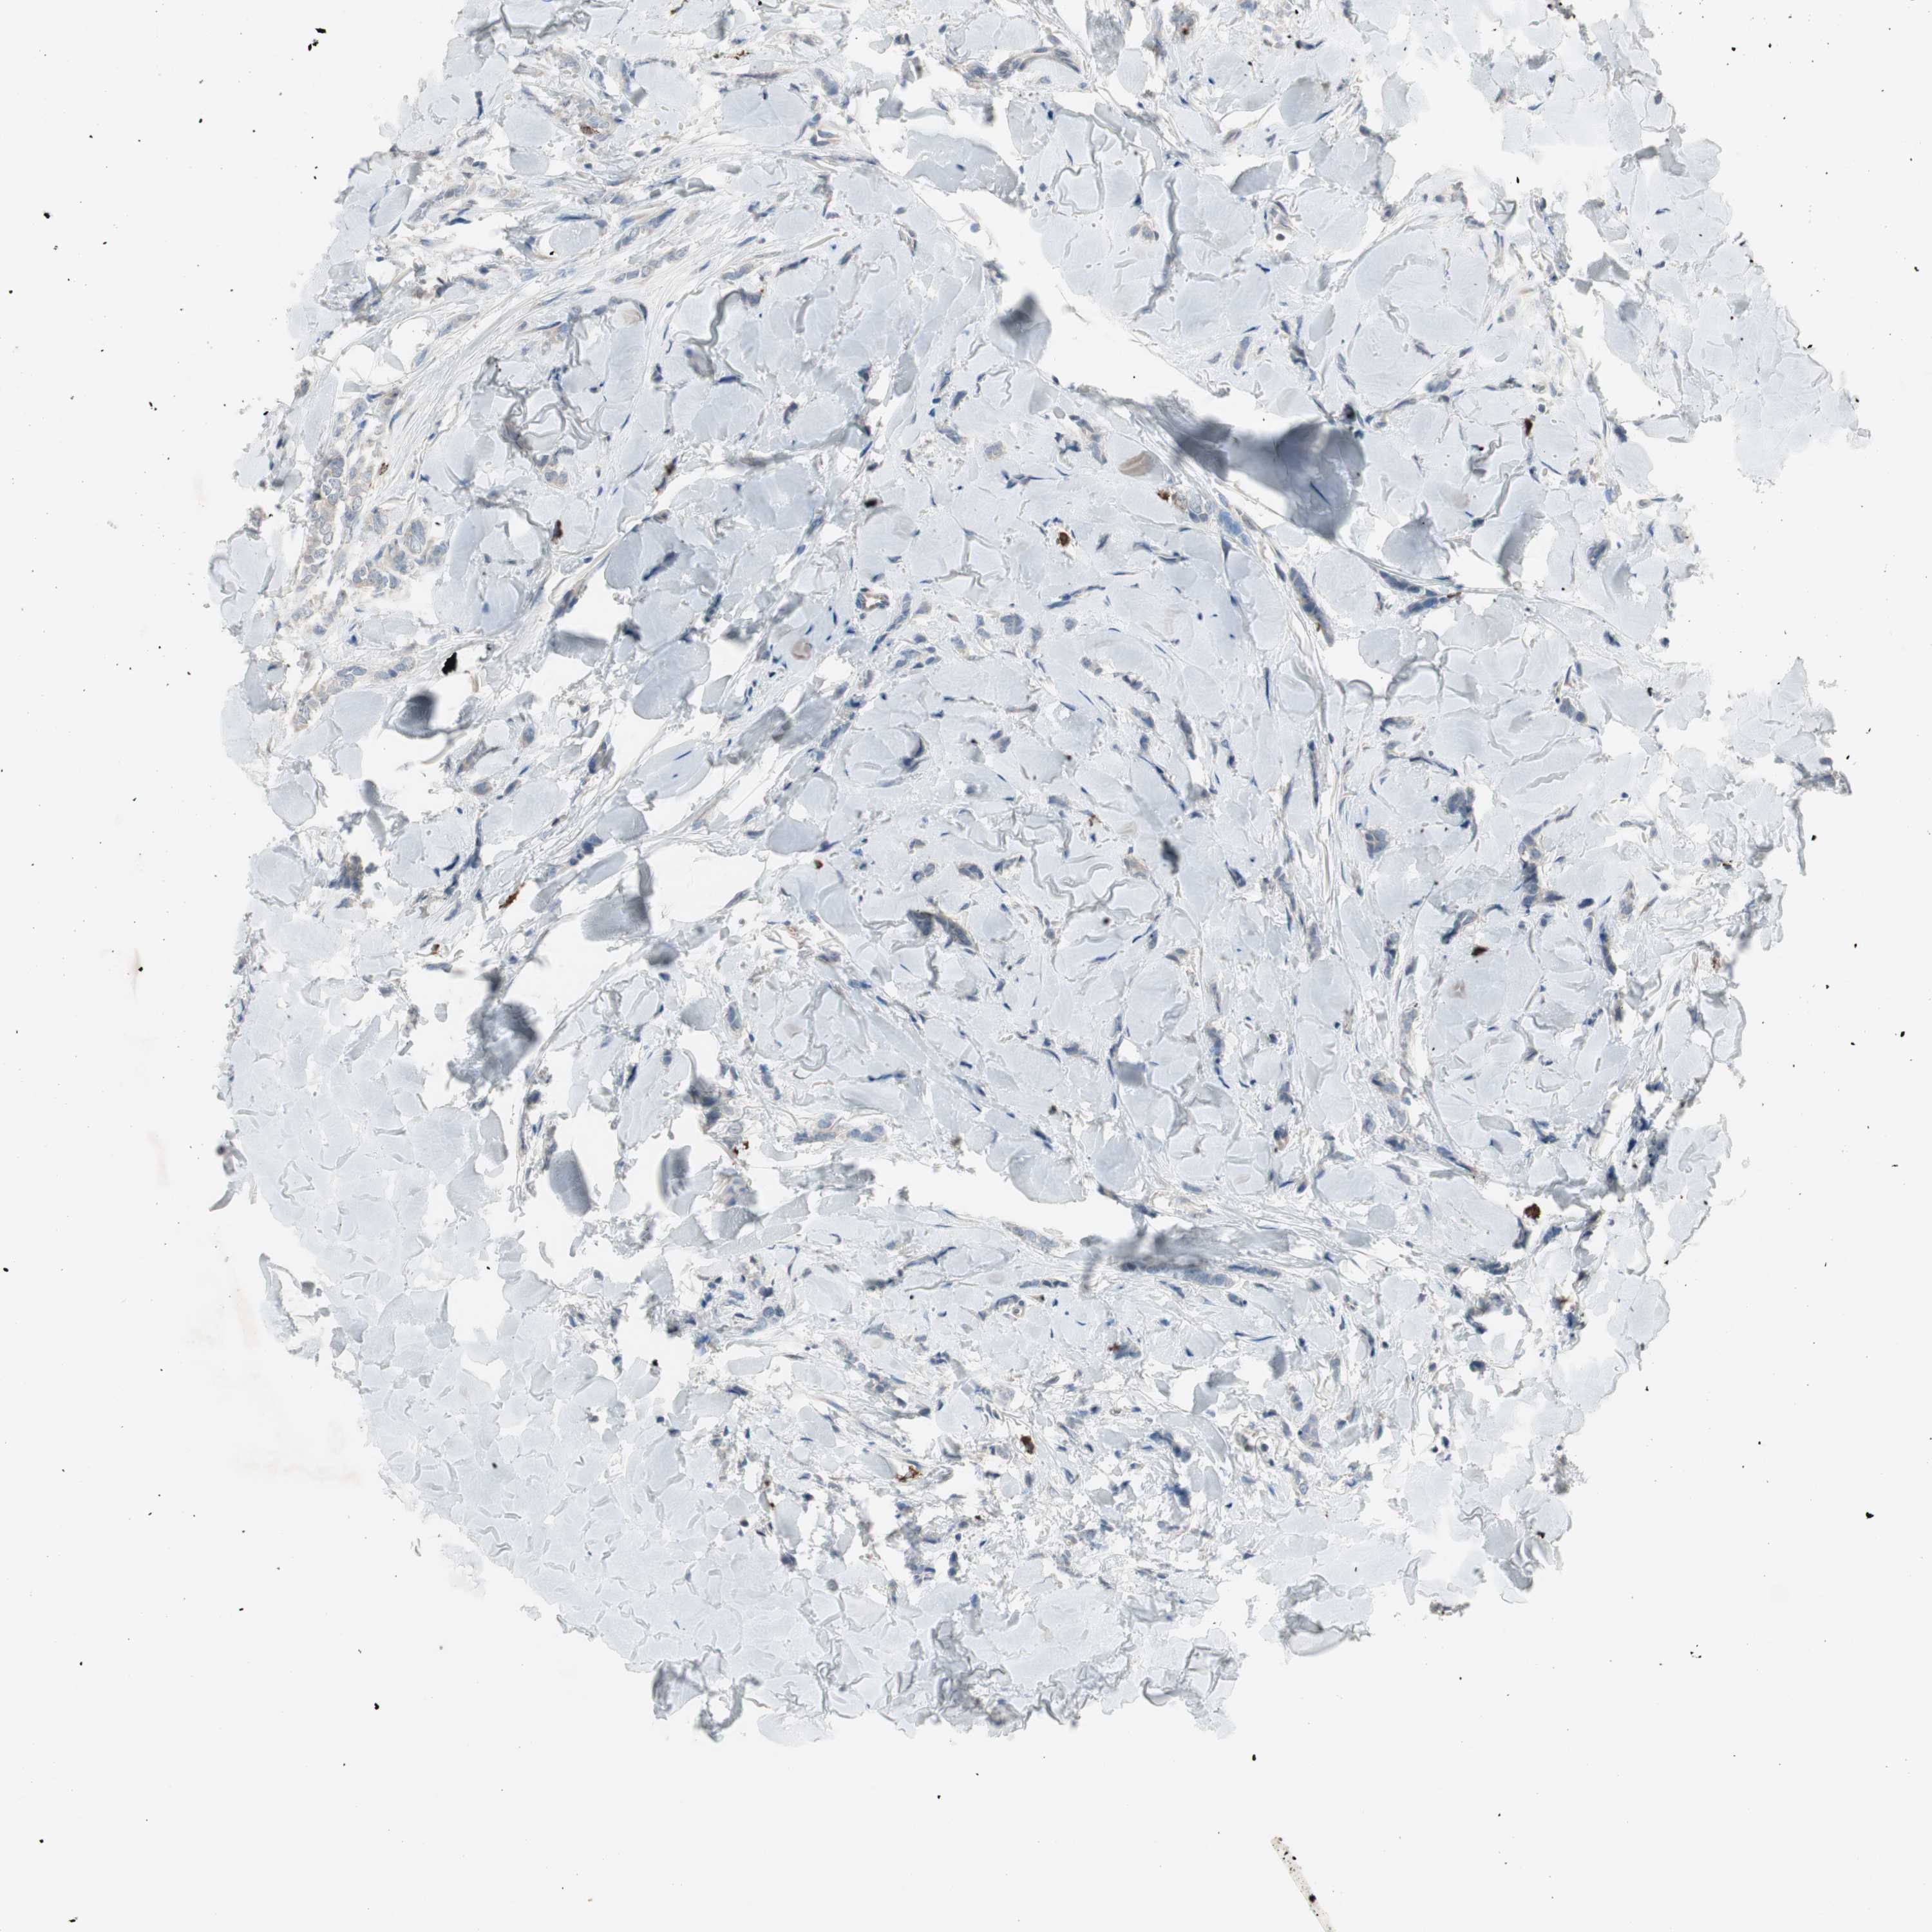

CANCER BREAST CANCER Show tissue menu

Breast cancer

Human cancer

MAPRE3 is not prognostic in Breast Invasive Carcinoma (TCGA)